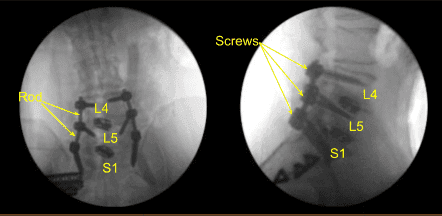

Loosening of bilateral sacral screws was confirmed and they were removed. We placed the neuronavigation array and fixed it rigidly to the posterior superior iliac crest with two Schanz pins.

The patient was draped sterilely. CT scan was obtained, and data was transferred to the neuronavigation computer. Neuronavigation techniques were used to reposition and replace bilateral sacral screws which were upsized both in diameter and length until tight.

We also replaced the left L4 and L5 pedicle screws similarly with a new track screw aided by decorticating with electric high-speed drill, cannulating with navigated pedicle finder, palpating for breaches, measuring the depth, under tapping by 1 mm and placing the pedicle screws without difficulty.

Additional CT scans were performed showing correct positioning of all the pedicle screw hardware. Neuromonitoring signals were stable. Next, we decorticated bilateral transverse processes and facet joints including sacral ala from L4 to S1 bilaterally with electric high-speed drill for the arthrodesis. The wound was irrigated copiously.

Precut-precontoured titanium rods were selected, contoured further and placed across the tulips from L4 to S1 bilaterally and secured with locking caps which were all final tightened with a torque and anti torque device. AP and lateral fluoroscopy was used to confirm appropriate sizing and positioning of the rods.